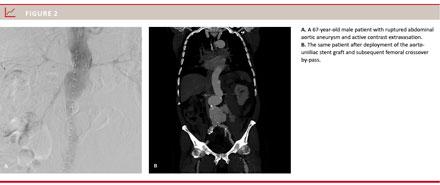

A total of 24 patients (89%) were men and three patients were (11%) women. Patients were aged 65-86 years (mean 74.4 years). The maximal AAA diameter ranged 6-12 cm (mean 8.1 cm). Two cases of ruptured common iliac artery aneurysms were included because of placement of an EVAR stent graft. Six (26%) patients were converted to general anaesthesia due to lack of cooperation or because they became haemodynamically unstable. In five (20%) cases, we chose a percutaneous approach from one side and in one (4%) case a total percutaneous approach. In all other cases (76%), bilateral groin cut-down was performed due to severe calcifications. A bifurcated stent graft was deployed in 26 (96%) of the cases (Figure 1A-C). In one case (4%), an aorto-uniiliac stent graft (Figure 2A-B) was employed followed by femoral crossover bypass.